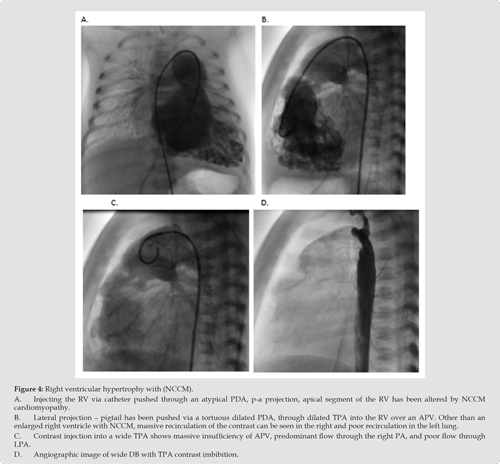

Consequently, they had RVH with suspicion of non-compaction right ventricular cardiomyopathy, more so in patient 4 than in patient 2 (Figure 1A-1D. – patient 2 and Figure 2A-2D-patient 4). Anomaly of ductus arteriosus is suspected in both of patients; in patient 2, a small, restrictive anomalous duct, through which only LPA is supplied, and which is separated from TPA (Figure 3A-3D - patient 2), in patient 4 there is an atypical, wide, tortuous arterial duct through which it enters the TPA, and then through the deficient PV into the RV. Massive insufficiency behind the trunk of the pulmonary artery towards the right ventricle is shown, and then the right ventricle with severe non-compaction cardiomyopathy (Figure 4A-4D - patient 4). In the other two patients, the ductus was not noted in the foetal cardiological examination. Interestingly, all pregnant women had problems during pregnancy; two had gestational diabetes mellitus and arterial hypertension, one had foetal hydrops and cystic hygroma (termination of previous pregnancy at 14 weeks), and one had a previous spontaneous abortion of unexplained aetiology. There is no information on any drug therapy during pregnancy.

One DA was aneurismatic dilated (Pat. 3), and one was atypically tortuous and wide (Figure 4, Pat. 4)). A ductal anomaly should also be suspected in the first patient (Pat. 1) who was born as a premature child, but it was not diagnostically verified in the period until it theoretically could have closed delayed (3 months after delivery), but a complete absence of the ductus is also possible because it is the socalled TF type of APVS. In addition to the aneurysmal expansion of the TPA, all patients also had marked dilatation of the RPA, and only one had extremely wide both branches of the pulmonary artery (patient 3). We note that as many as three patients had hypoplasia of the left branch of the pulmonary artery (patients 1, 2, 4) (Figures 3 & 4), and patient 2 had extreme hypoplasia of the LPA, which filled through the restrictive DB, and was initially completely separated from the RPA. In patient 3, in whom VSD was mentioned prenatally, we did not find it postnatally, and two patients (pat. 1,2) had right-sided anomalies with subaortic VSD. We did not use the term TF anywhere with certainty because we believe that the basic characteristic of TF is a significantly smaller pulmonary artery than the aorta, while our patients with VSD (pat. 1 and 2) had a significantly wider PA than the aorta. The mean pulmonary artery pressure (mPA) in one patient (pat. 1) was 31 mmHg (measured at the age of 11 months), and the other patients had mPA below 25 mmHg. (pat. 2,3,4).